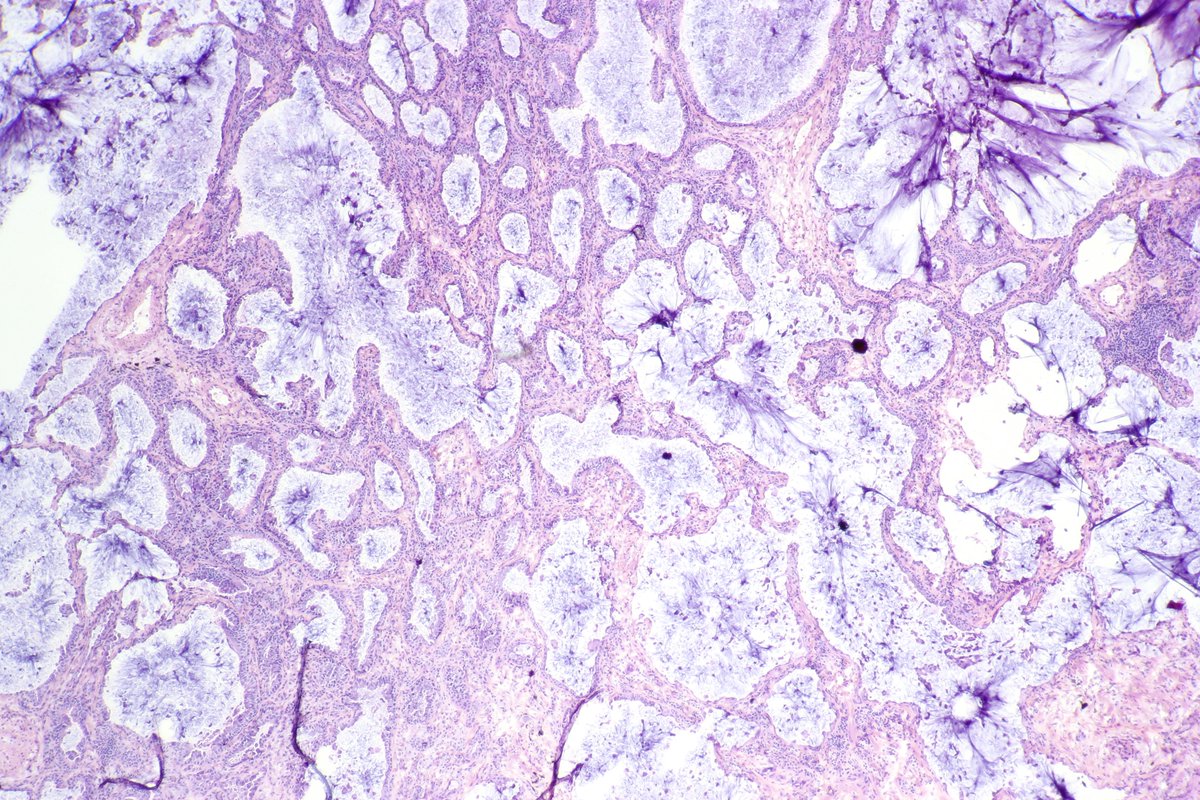

Atypical carcinoid of the lung exhibiting endobronchial growth, increased mitotic activity was seen (2-10 per 10 HPF). #pathology #PulmPath